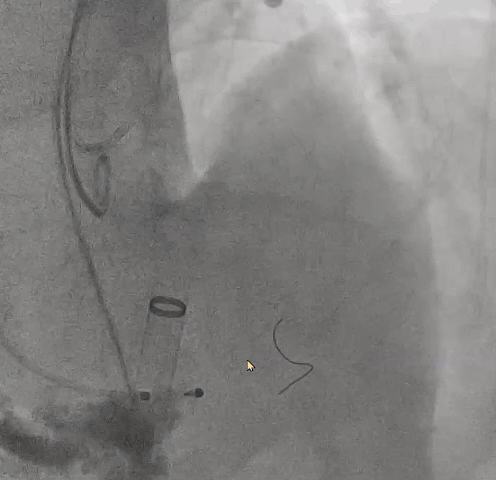

行左冠保护,预置左冠球囊

● 更换新瓣膜跨瓣后,猪尾难以送至无冠窦底,故行造影定位窦底。

隐约可见“无冠窦”后部更深窦底,位于“无冠窦”下约6mm,参考该位置后进行0位定位,无起搏逐步释放至工作位,瓣膜无明显位移表现,瓣膜形态压缩良好,造影评估无反流。准备释放瓣膜。

无张力释放,脱钩后瓣膜略微下滑,约位移瓣环下4~5mm位置,瓣膜整体形态良好,造影评估无可见反流。